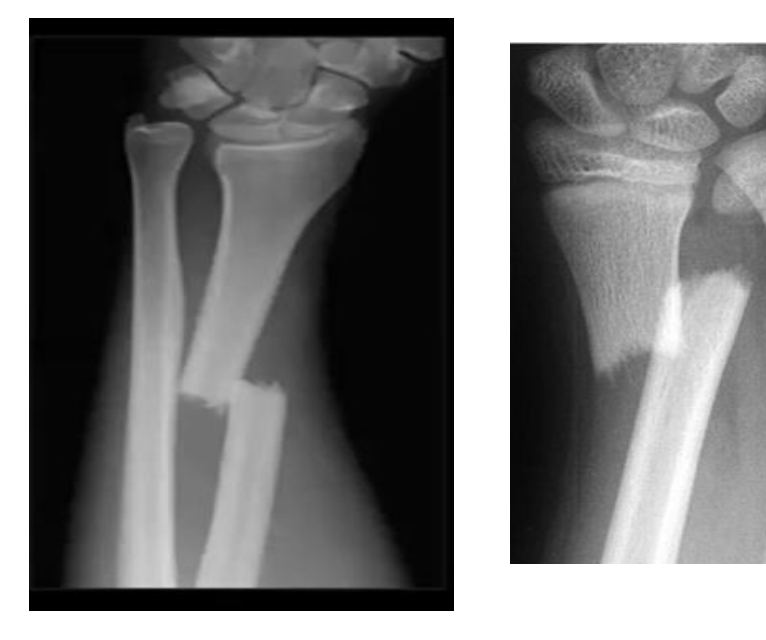

type of fracture ?

/

SAY everything